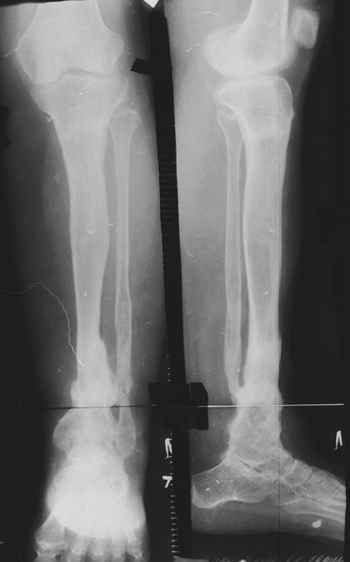

Женщина 28 лет, пошедшая 13 предыдущих оперативных вмешательств по-поводу ВПБ имела 9 см. укорочения.

На первом этапе аппаратом Илизарова закрыто устранена деформация голени.